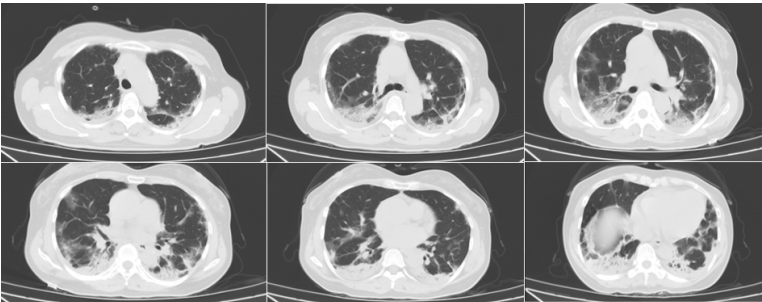

影像学:8月22日胸部CT见少量渗出(图1)。8月31日复查胸部CT可见大量弥漫渗出(图2),病情进展迅速。

图片

图1  患者胸部CT(2020-08-22)

图2  患者胸部CT(2020-08-31)